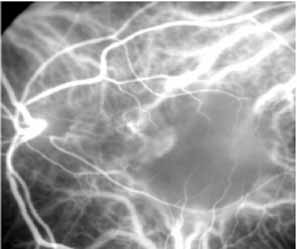

In the early phases of ICG angiography, patients with central serous chorioretinopathy (CSC) demonstrate widespread choroidal vascular hyperpermeability71,72 (Fig. 20). These permeability abnormalities may precede visual symptoms or detectable clinical and fluorescein angiographic changes. Although diffuse leakage from the choriocapillaris is clearly noted on the ICG study, focal active leaks at the level of the retinal pigment epithelium remain better defined on fluorescein angiography.

Fig. 20 Composite photo of a patient with central serous chorioretinopathy. The extensive areas of hyperfluorescence represent areas of presumed choroidal hyperpermeability.